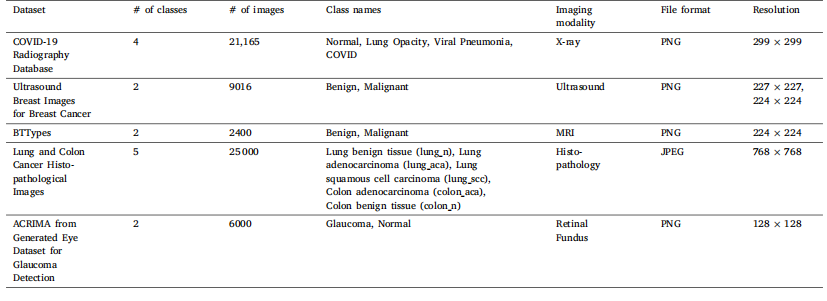

This section introduces information about the experiments performed and the results produced in this study. This section also prvides additional information about the datasets, experimental setup,optimized hyper-parameters, and evaluation metrics used in this study.

本节介绍本研究中开展的实验及其产生的结果,还提供了关于本研究中使用的数据集、实验设置、优化的超参数和评估指标的额外信息。

Table 3Summary of the datasets used in this study

表3 本研究中使用的数据集摘要。